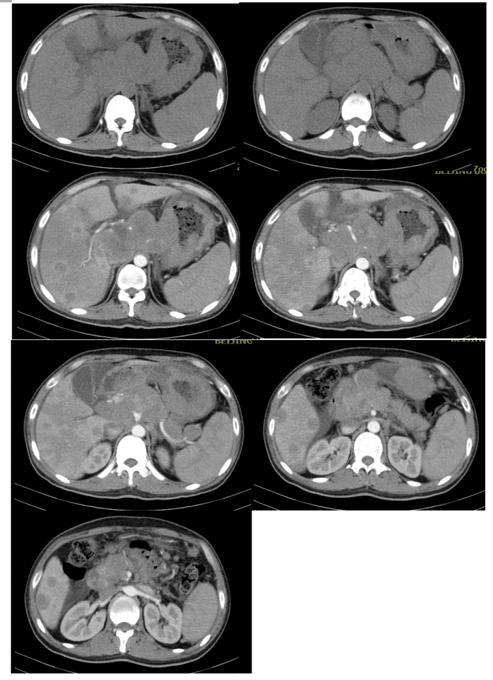

腹部增强CT(如下图一所示):肝脏、胃、腹腔及腹膜后多发淋巴瘤(腹腔、肝门区及腹膜后见多发肿块影.增强后轻度强化,融洽成大块,大小约85X110X97mm,肿块与胰腺关系密切)。2、腹腔少量积液

图一

2020-4-20复查腹部增强CT(图三所示):腹腔、肝门区及腹膜后见多发肿块影.增强后轻度强化,融洽成大块,大小约40X43X44mm,较前明显缩小,肿块与胰腺关系密切,主胰管无明显扩张.胃壁不规则稍增厚并强化。

图三

通过上述影像学变化我们可以看到BV-IVE方案治疗后,患者瘤灶明显缩小(如上图三)。该患者经过减瘤治疗后续进入CAR-T治疗。从此病例我们可以看出CD30阳性的弥漫大B患者,对BV的治疗反应还是比较好的。